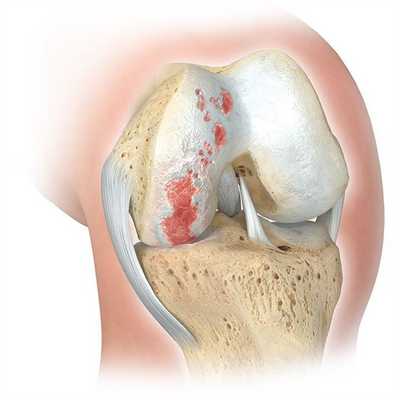

Если сустав поражен указанным на изображении образом, то возможна его частичная замена.

Основной метод лечения – постановка эндопротеза вместо поврежденного сустава. Раньше выполнялось преимущественно тотальное эндопротезирование коленного сустава, однако сейчас активно развивается другое направление – одномыщелковое (частичное) эндопротезирование.